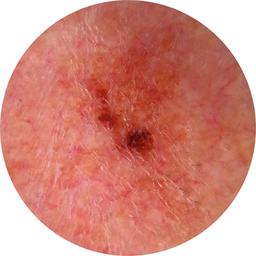

ISIC_7740426

1172 x 1172

Clinical

Field Value

acquisition_day 278

age_approx 65

anatom_site_1 Head and neck

anatom_site_general head/neck

diagnosis_1 Benign

family_hx_mm False

image_manipulation instrument only

image_type dermoscopic

lesion_id IL_9049639

patient_id IP_3152710

personal_hx_mm True

sex male